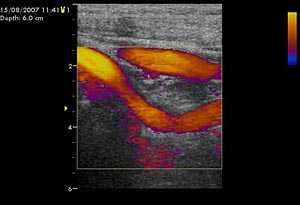

Рис. 1. Дуплексное сканирование сонных артерий.

При физикальном обследовании определялось опухолевидное образование размером 6х4 см, с гладкой поверхностью, плотно-эластической консистенции, безболезненное, малоподвижное. По данным ультразвукового дуплексного сканирования внечерепных отделов брахиоцефальных артерий в левой подчелюстной области было выявлено округлое образование, в капсуле, размерами 62х41х37 мм, со слабой васкуляризацией по стенкам и в центре опухоли, не связанное с сонными артериями.

Образование принадлежит к латеральной стенке левой каротидной бифуркации и передне-латеральной стенке проксимальной порции левой внутренней сонной артерии. Также отмечалась С-образная извитость левой внутренней сонной артерии, вызванная механическим сдавлением объёмным образованием (рис.1).